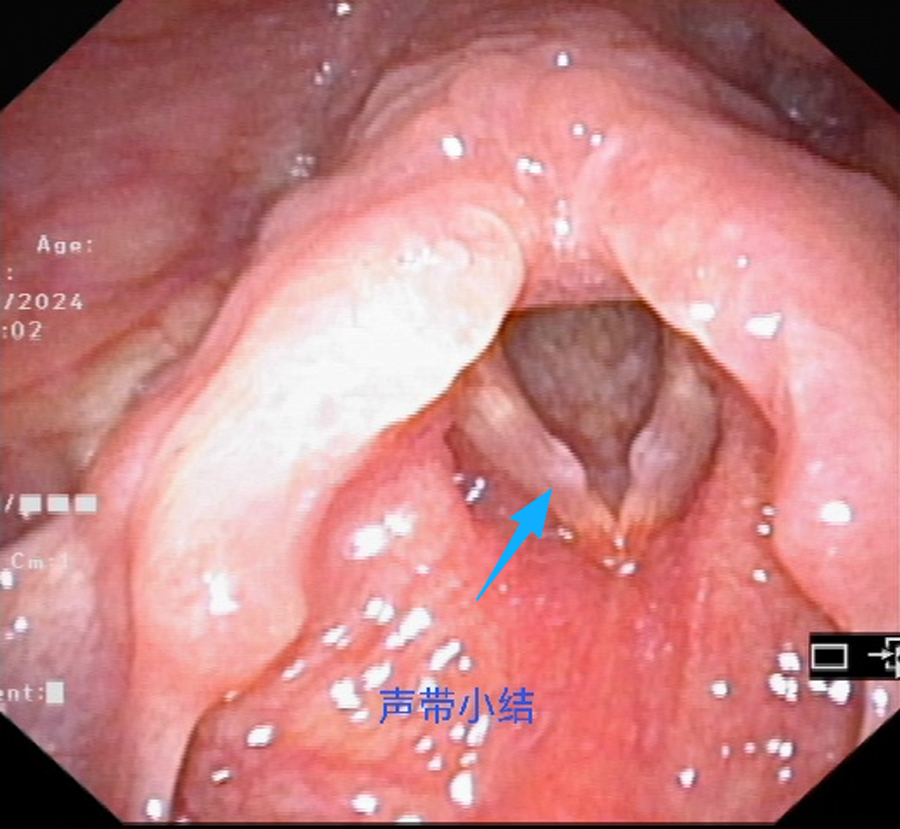

“喊叫小结”(声带小结):最常见的一种。孩子总爱大喊大叫,声带反复摩擦,就像手上磨出茧子,时间长了声带上长出“小疙瘩”,导致声音持续嘶哑,说话费劲。